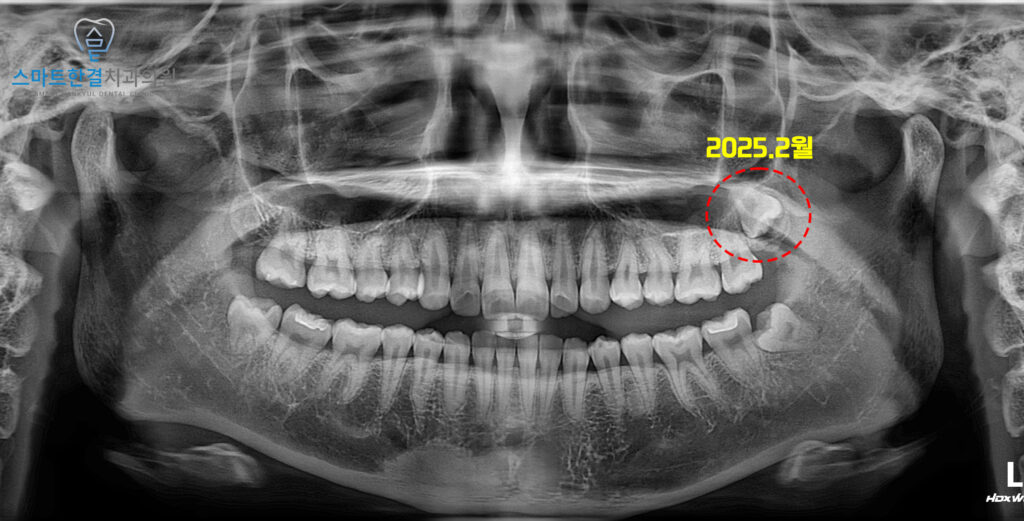

2025.2월

<위쪽 사랑니 낭종 발견>

위 환자분께서는 정기검진을 위해

본원에 내원해 주셨어요.

정밀한 검진을 위해

파노라마를 촬영해 보았는데요.

왼쪽 위 매복 사랑니가 관찰되었고,

사랑니 주변으로 비교적 경계가 뚜렷한

낭종성 병소가 함께 확인되었어요.

당시에는 자각 증상이 없고

낭종의 크기도 크지 않은 상태였기 때문에,

즉각적인 수술적 처치보다는

정기적인 경과 관찰을

우선적으로 시행하기로 하였답니다.